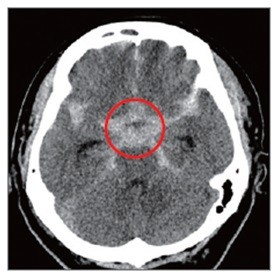

뇌동맥류로 인해 부풀어 오른 혈관이 터지면 뇌출혈이 생긴다. 이 경우 사망 위험이 크게 증가하고 뇌에 영구적 손상이 가해져 언어장애, 운동장애 등이 유발된다.

검사는 주로 뇌혈관 CT(CTA), 뇌혈관 MRI(MRA) 검사, 뇌혈관조영술 등으로 한다. 파열 전 증상으로 주로 둔기로 맞은 듯한 극심한 두통, 뒷목이 뻣뻣해지는 증상, 구토 등이 있을 수 있고 심한 경우 마비, 의식소실, 호흡마비 등이 나타난다. 따라서 한 번도 겪어보지 못한 두통 등이 있다면 즉시 병원을 찾아야 하고 때로는 드물지만 감기증상처럼 가벼운 두통이 수 일간 지속될 수 도 있기 때문에 유의해야 한다.

뇌동맥류를 파열 전 발견해 치료하면 95% 이상에서 좋은 결과가 나타난다. 치료는 주로 ‘클립결찰술’과 코일색전술’로 이뤄진다. 클립결찰술은 이마 부위 두개골을 열고 클립 같은 고정 핀으로 부풀어 오른 뇌동맥류를 졸라매는 수술법이다. 코일색전술은 머리를 절개하지 않고 사타구니에 있는 대퇴동맥을 통해 뇌동맥에 가느다란 도관을 넣은 뒤 뇌동맥류 내부를 백금 등으로 만들어진 특수 코일로 채워 막는 방식이다. 뇌수술이 어렵거나 직접수술이 위험성이 큰 환자에게 적합하다.